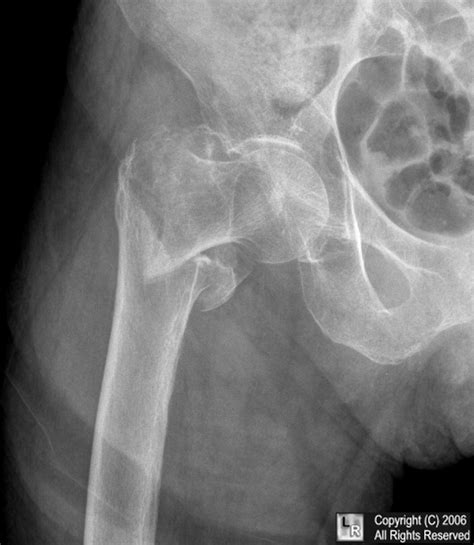

The lesser trochanter of the femur is a conical eminence, which varies in size in different species. Twelve weeks after the injury the patient resumed his normal sport activities. Isolated fractures of the lesser trochanter are. Avulsion fractures of the lesser trochanter in adolescents are uncommon. A recent case series (of only five patients) showed that the mean age of patient that presented with this injury.

Avulsion fractures of the lesser trochanter in adolescents are uncommon. Lesser trochanter avulsions are almost always the result of an underlying pathologic lesion. Avulsion fractures of the lesser trochanter in adolescents are rare. Twelve weeks after the injury the patient resumed his normal sport activities. A positive ludloff sign—the inability to raise the thigh when in a sitting position— is seen with injuries involving the iliopsoas muscle. The lesser trochanter is a growth region type apophysis, where is attached the illiopsoas muscle. There is little literature to guide their treatment. Chronic avulsion fracture of the anterior inferior iliac spine, origin of the straight head of the rectus femoris muscle.

They are a result of a sudden and forceful contraction of the iliopsoas muscle. An isolated fracture of the lesser trochanter is rare and may occur as an avulsion fracture of the iliopsoas muscle at a young age. @article{vazquez2013avulsionfo, title={avulsion fracture of the lesser trochanter: Implant failure occurs within the first three months. Pelvic, pelvis, avulsion, fracture, athlete, hurdler, sprinter, runner, radiology. Therefore we aimed to report these in the present study. Twelve weeks after the injury the patient resumed his normal sport activities. The lesser trochanter is a growth region type apophysis, where is attached the illiopsoas muscle. Lesser trochanter avulsion, apophysis, groin pain. There is little literature to guide their treatment. The patient we report presented with pain and limited hip flexion. The position of the lesser trochanter close to the head of the femur is one of the defining characteristics of the prozostrodontia. There is fluid and hematoma around the iliopsoas tendon.